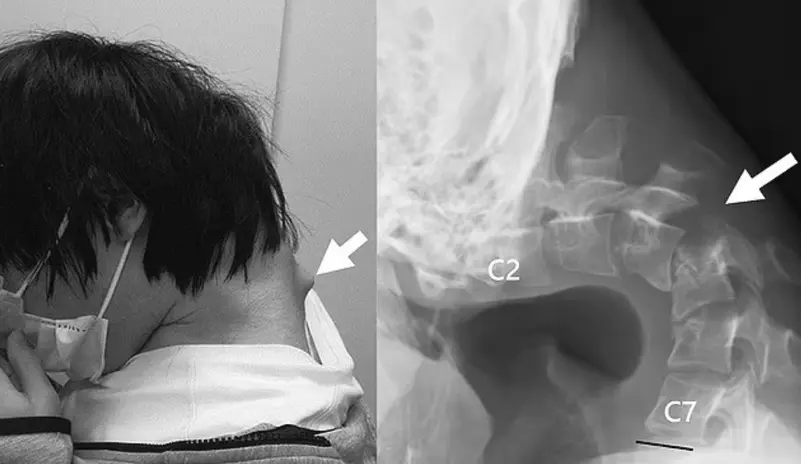

وكشفت صورٌ كيف يُمكن أن يُؤدي قضاء ساعات في لعب الألعاب على الهاتف الذكي إلى "متلازمة الرأس المتدلي" المُرعبة والتي تؤدي بالشخص إلى الانحناء المزمن والمستمر طوال عمره.

وتُظهر الصور انتفاخاً بارزاً من رقبته، والذي عزاه المُسعفون إلى "تمدد فقراته بشكل كبير" عن الوضع غير الطبيعي.

وكشفت صور الأشعة التي أجراها أطباؤه أن فقرات رقبته قد تشوهت وانخلعت، مما أدى إلى نمو أنسجة تشبه الندبات في العمود الفقري بمرور الوقت.